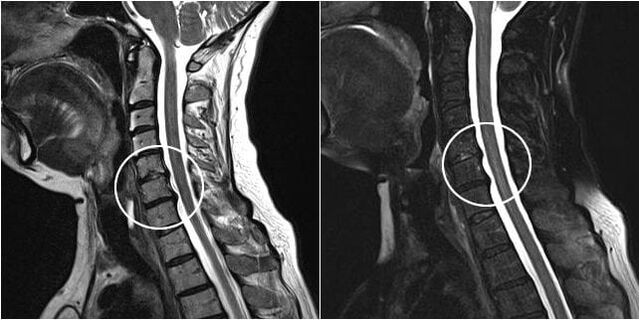

Man mano che i dischi intervertebrali e le vertebre si deformano, le condizioni del paziente peggiorano. Il decorso dell'osteocondrosi è complicato da sintomi neurogeni causati dalla compressione da parte degli osteofiti o dalla protrusione erniata delle radici spinali e dell'arteria vertebrale. Si verificano mal di testa, vertigini, cambiamenti della pressione sanguigna e diminuzione dell'acuità visiva e uditiva.

Le indicazioni per l'intervento chirurgico comprendono l'inefficacia del trattamento conservativo e le complicanze dell'osteocondrosi cervicale, ad esempio la mielopatia discogenica, la sindrome dell'arteria vertebrale e la sindrome radicolare. Per alleviare il carico sul midollo spinale, sui vasi sanguigni e sulle radici spinali, vengono eseguite le seguenti operazioni: